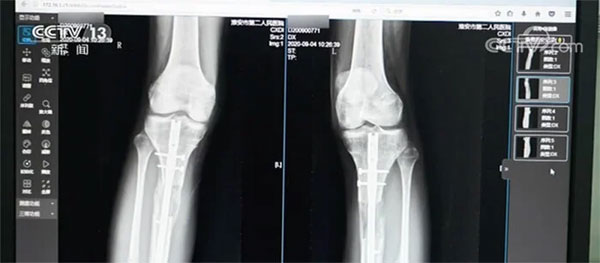

Ngoài Tiểu Hi và Tiểu An, có không ít người khác phải gánh chịu hậu quả nặng nề sau phẫu thuật tăng chiều cao. Năm 2020, Bệnh viện Nhân dân số 2, thành phố Hoài An, Giang Tô (Trung Quốc) tiếp nhận một bệnh nhân nam 22 tuổi. Vì không hài lòng với chiều cao của mình, anh đã ra nước ngoài làm phẫu thuật kéo dài chân và sau đó là đôi chân bị nhiễm trùng nặng. Anh không thể đi lại, thậm chí còn phải đối mặt với nguy cơ tàn tật suốt đời.

Năm 2022, thời báo Red Star cũng kể câu chuyện một cô gái 19 tuổi ở Nam Xương, Giang Tây sở hữu chiều cao ban đầu là 1m54, sau phẫu thuật kéo dài chân thì cao thêm 6cm nhưng luôn gặp khó khăn khi đi lại. Qua thăm khám, bác sỹ phát hiện khớp gối và mắt cá chân đã cứng lại khiến cô không thể tự mình đứng vững mà phải nhờ đến nạng.